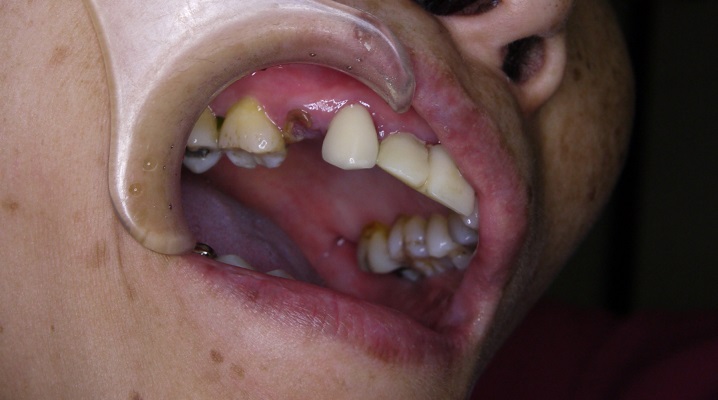

之前很害怕植牙手術的她

鼓起勇氣來把斷掉的牙齒拔掉

她的骨頭條件等各方面都還不錯

醫師建議她當天現拔現種,當然,